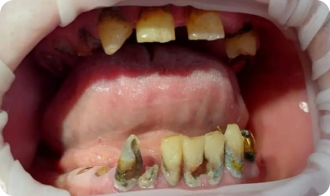

Установка All-on-4

До приёма:

• Полная адентия зубов

• Атрофия костной ткани

Результат:

• Установка имплантов Nobel

• Костная пластика

Срок: 2 дня